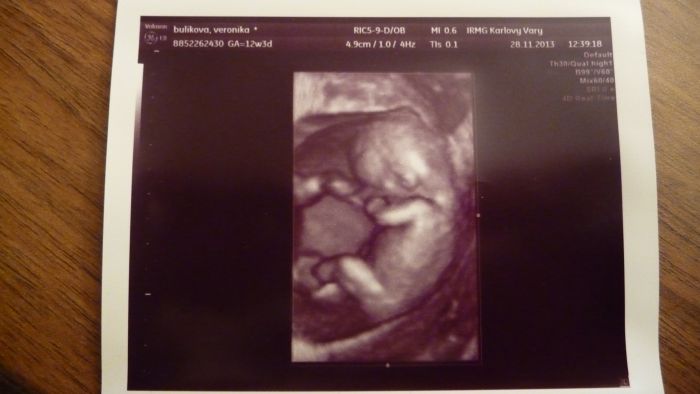

jeste pridavam foto nasi princezny a dneska jsem se rozhodla a bude se jmenovat Ellen.....tata bude mit radost az na kost a moje sestra taky, ti dva totiz jmeno vymysleli

Marti, krásná fotečka!

[397014] Martasku a v kolikatem jsi? Ja jsem 12+4 a nemam z dneska tak hezkou fotku. 3D úplne nepoznatelny a normální docela pěkný, ale třeba nozicky nejdou v podstatě videt.

Ahojte těhulky, tak jsem dnes byla na screeningu, KONEČNĚ... ALE... čekám prý flegmatické spací mimčo

Doktor do mě bušil, musel mě vyšetřit vaginálně a mímo pořád spinkalo, vždy se jen zavrtělo, jako že nech mě a zase spinkalo. Vypadá prý vše ok, krev budou volat jen pokud něco objeví. Tak snad to bude také OK. Jinak máme 4,64 cm a Dr. mi řekl, že nejspíš nebudu v tom 12tt ale asi v 10tt. Tak nevím. Posune se mi TP, tak příští pondělí jdu na kontrolu k mé Dr. tak písnu. Srdíčko jsme s přítelem slyšeli a bylo to úžasné. Pohlaví nevíme, prý se nám správně nenatočila a je ještě brzy. Ale dva známí tatínkové na to koukali a bylo jim hned jasno. Viděli holčičku.

Tak snad se chlapáci taťáci nemýlili. Přítel byl na screen. celou dobu semnou a byl nadšený, nejvííc ze zvuku srdíčka. Mám 4 fotky a to jen proto, že to malé jen spalo, tak ho Dr. aspoň fotil. Bylo nádherné vidět toho tvorečka, jak si dává ručičky k obličeji a za hlavu. Jednu nožičku mělo nataženou a druhou pokrčenou. Jsem šťastná. Gratuluji maminám co ví už pohlaví.